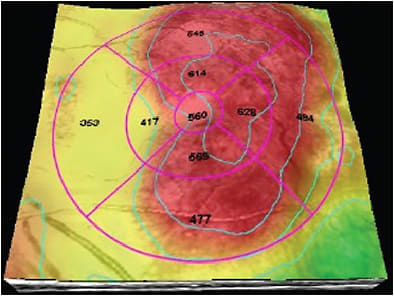

Optical coherence tomography is ordered to study the histological status of the macula and the vitreomacular interface integrity. OCT is important in cases of DME with foveal involvement to study the central retinal subfield thickness. Because central macular thickness may not have a great impact on VA, it may play a role in choosing and monitoring treatment (Figure 6).17

Figure 6. Diabetic macular edema with central involvement and increased central retinal subfield thickness.

OCT mapping can be used to locate edema, providing information that can be used for modified grid or focal laser treatments.13 OCT is also an important method to monitor the efficacy of treatment reduction of central retinal subfield thickness, which along with improved BCVA may indicate successful treatment.19